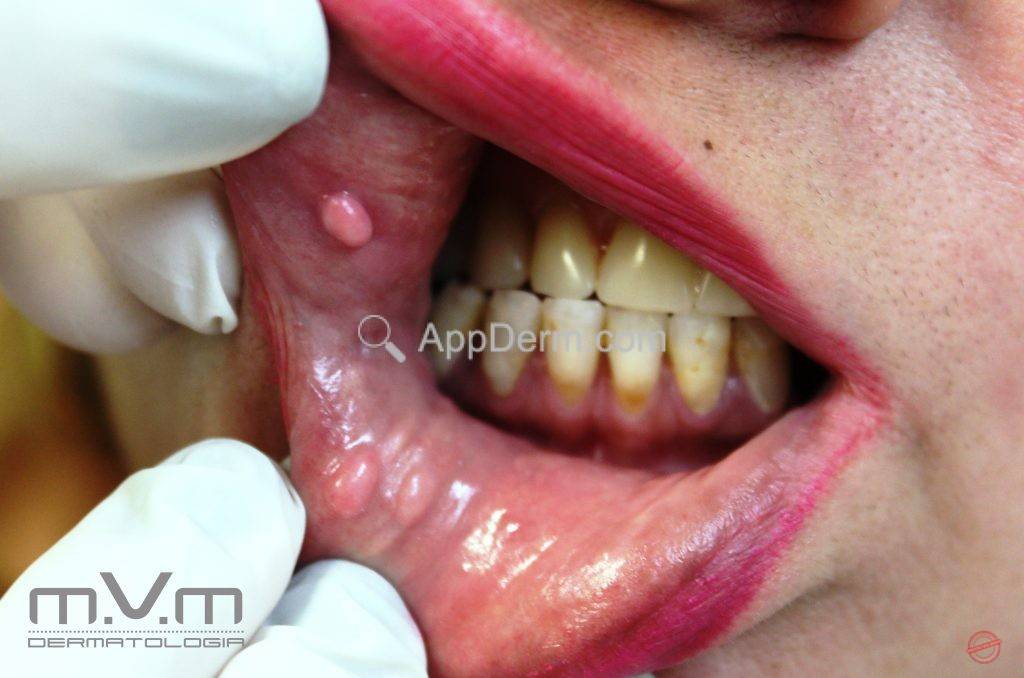

Doença de Heck (hiperplasia epitelial focal)

Doença causada pelo papiloma vírus humano (HPV), subtipos 13 ou 32.AppDerm®